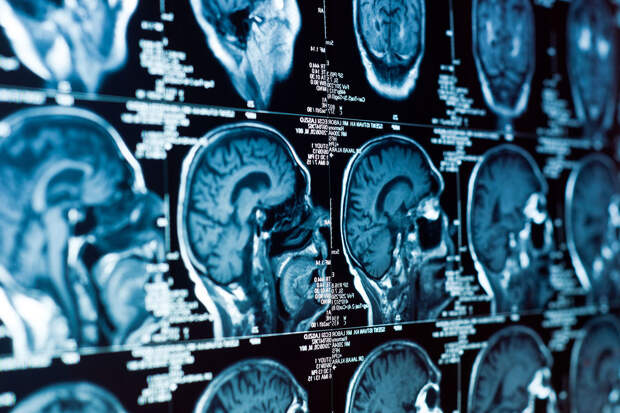

Ученые из Пенсильванского университета выяснили, что стресс способен вызывать нарушения кровотока в мозге. Этот фактор способствует развитию болезни Альцгеймера. Результаты исследования опубликованы в журнале eLife.

Удаление этих нейронов у животных также приводило к снижению как кровотока, так и электрической активности мозга, особенно во время сна. Это, по словам ученых, доказывает, что nNOS-клетки играют ключевую роль в снабжении мозга кислородом и поддержании нейронных связей.

"Снижение кровотока — один из факторов, ускоряющих ухудшение работы мозга и развитие нейродегенеративных заболеваний у людей. Потеря этих редких нейронов из-за хронического стресса может быть недооцененной причиной такого ухудшения", — отметил ведущий автор исследования, профессор инженерных наук Патрик Дрю.